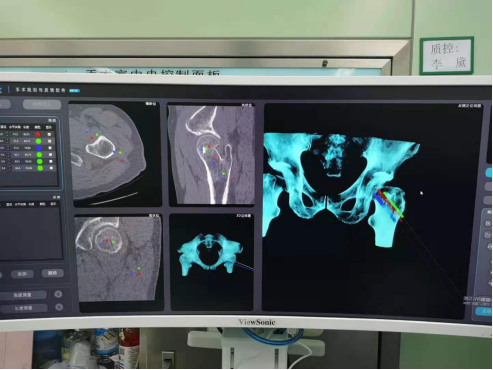

术前规划

手术中精准置钉